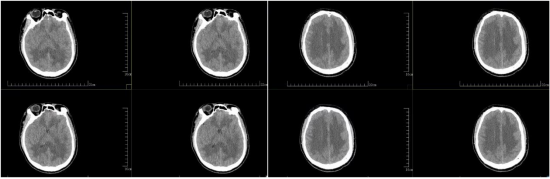

3月20日,小李迅速陷入昏迷。在日喀则就医后,病情持续恶化,相继出现昏迷程度加深、反复肢体抽搐、去大脑强直状态,被确诊为急性重症高原性脑水肿,合并严重高原性肺水肿。

入院检查评估显示,小李格拉斯哥昏迷评分仅6分,病情极其危重。低压低氧环境引发的严重脑水肿、肺水肿快速进展至呼吸衰竭,他随时面临呼吸心跳骤停、脑死亡、猝死风险,生死一线。

面对这名年轻危重患者,西安高新医院神经外科高度重视,第一时间启动危重症救治预案,紧急开展病例研讨,严格遵循重症高原病诊疗指南,迅速展开全方位抢救。神经外科医护团队为他实施了一系列精准治疗:高流量吸氧纠正低氧血症、脱水降颅压减轻脑水肿、糖皮质激素冲击治疗抑制炎症反应、冰帽亚低温脑保护及亚低温代谢调控降低脑耗氧量、高压氧疗促进脑功能恢复。

然而,小李的病情仍在加重。随着脑水肿和肺水肿持续进展,最终发展为呼吸衰竭。神经外科医护团队果断为他实施气管切开术,连接呼吸机行生命支持治疗。整个救治过程中,医护人员24小时严密监护、动态调整治疗方案,全力守护这条年轻的生命。

经过为期3周的不间断精心救治与重症监护,小李的生命体征逐步平稳,意识慢慢恢复清醒,抽搐症状完全消失,肺部、脑部水肿持续消退,顺利脱离呼吸机支持,逐步恢复自主呼吸,能够下床活动。目前,小李各项身体指标回归正常,病情痊愈,即将康复出院。